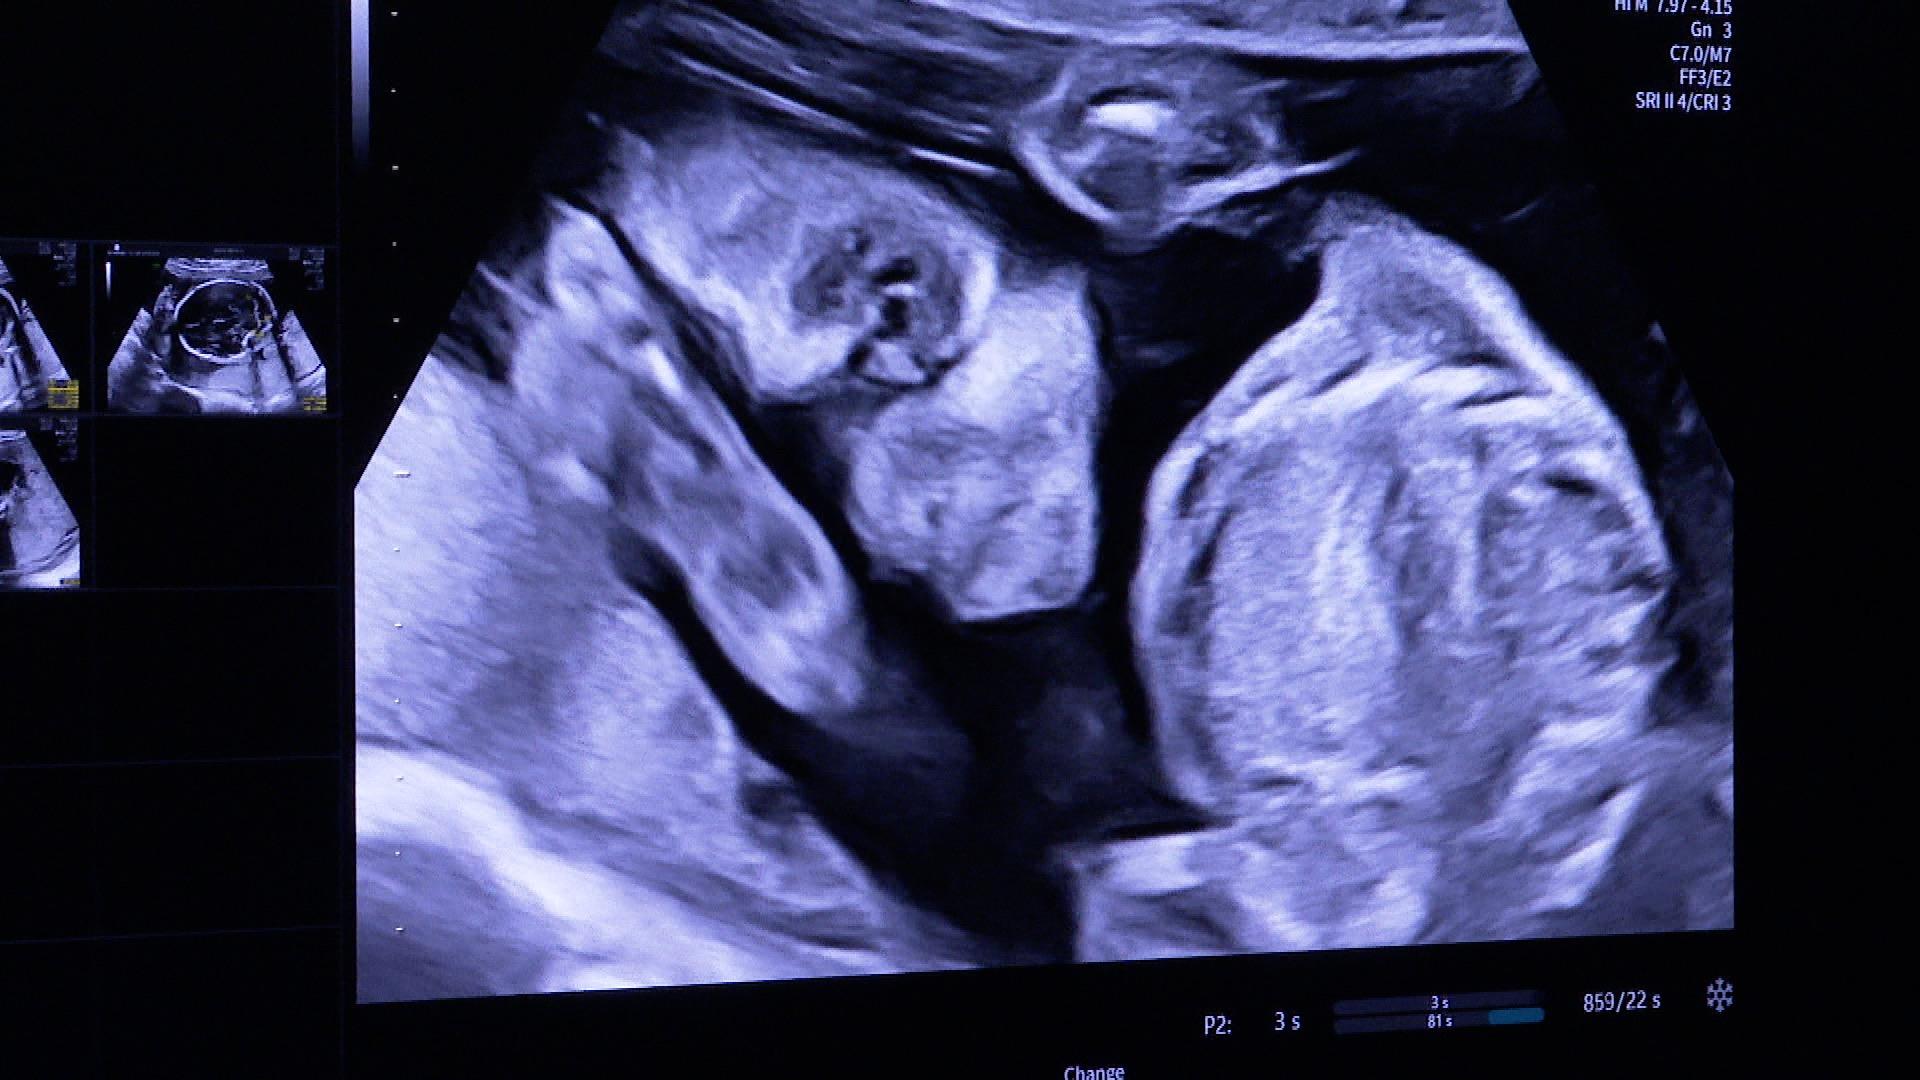

Ma már az új genetikai ultrahanggal vizsgálták a kismamákat. A mesterséges intelligenciával támogatott eszköz a korábbinál jóval részletesebb képet ad, számos automatikus beállítása segíti a pontos diagnosztikát. A 75 millió forintos készüléket ünnepélyes keretek között adták át.

Két okból is hatalmas előrelépést jelent. Egyrészt azért, mert ez egy csúcsminőségű ultrahang, közel bruttó 75 millió forint értékben. Több fejjel és így 3D-s, 4D-s ultrahang vizsgálatra is alkalmas. Tehát alkalmas arra, hogy meddő párokat kivizsgáljunk, hölgyeket és férfiakat is, és arra is alkalmas, hogy magzati, genetikai szűrővizsgálatok történjenek